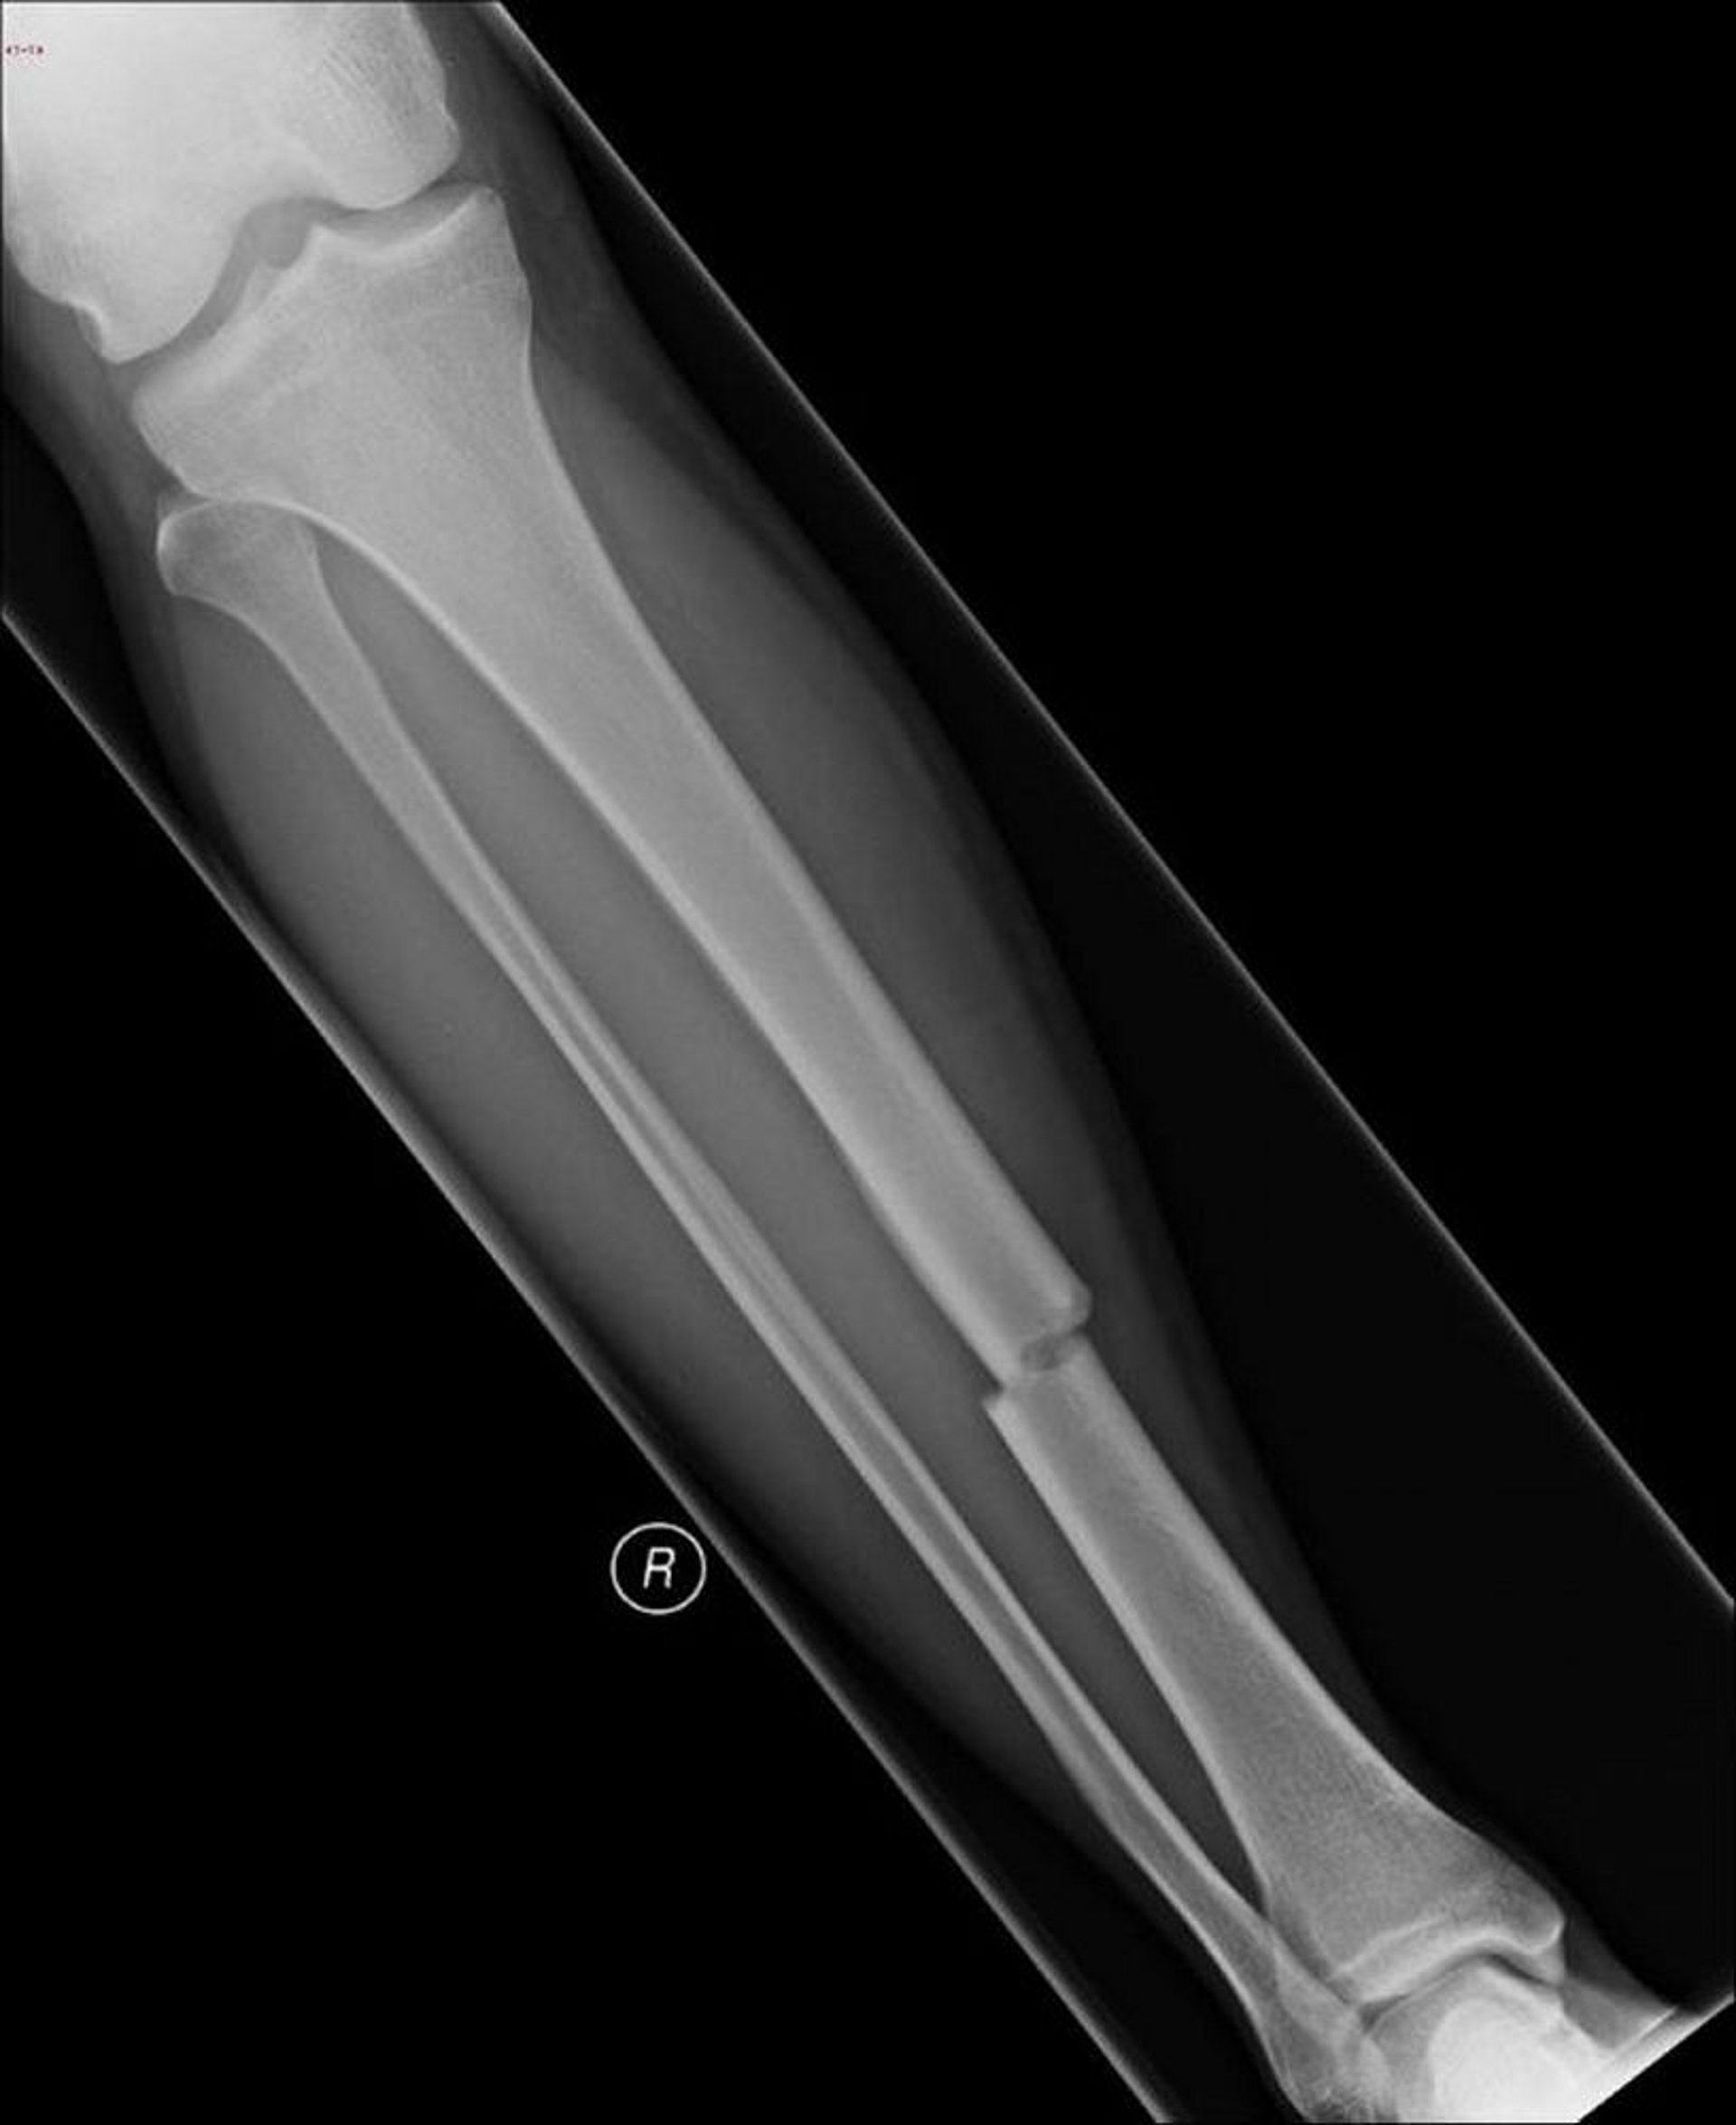

Esta radiografía muestra una rotura en el centro de la tibia.

Imagen cortesía de Danielle Campagne, MD.